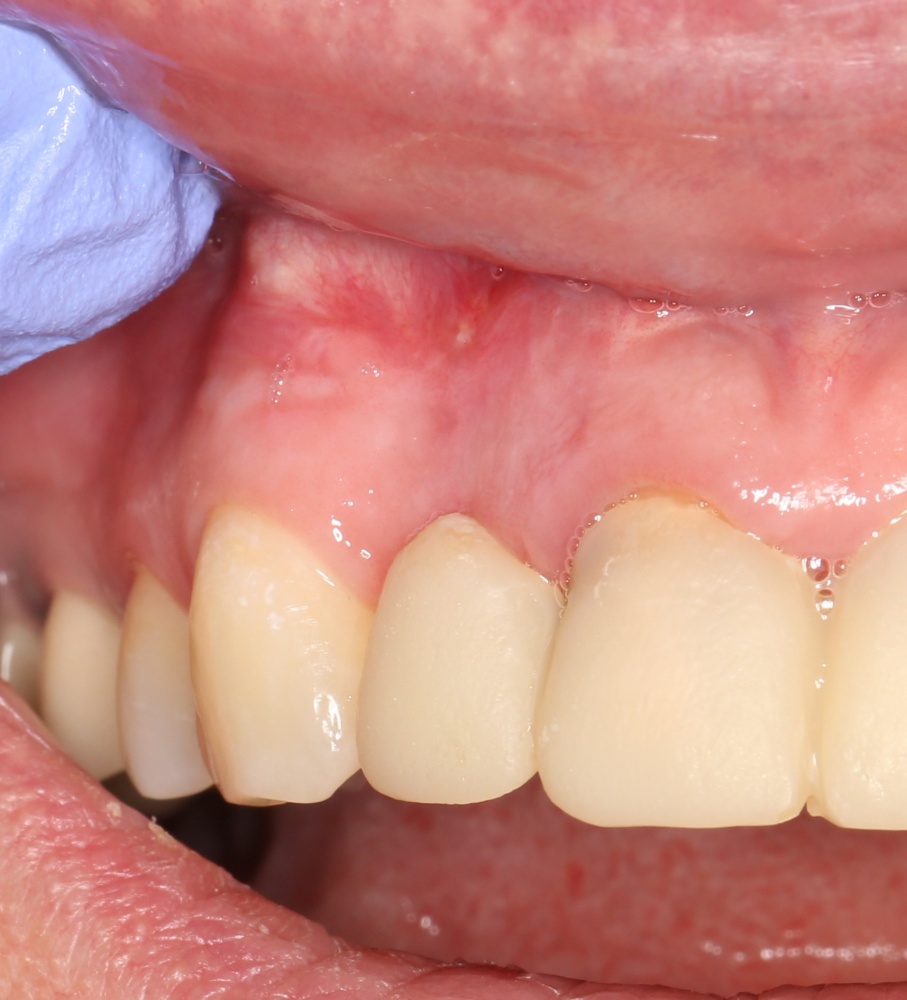

Устанавливаем формирователи десневой манжеты. Сегодня я называю эту процедуру не менее важной, чем любой другой этап имплантологического лечения:

И швы. Просто швы. Никаких дополнительных процедур.

Если честно, то сейчас бы я использовал другой шовный материал и другой тип швов. Одно неизменно, — и я об этом много раз говорил, — самая широкая часть формирователя десны должна находиться на уровне десны. Так, чтобы эффективно отрабатывать т. н. «биологическую ширину».

Через неделю я снял швы, а мой коллега Андрей Карнеев (дело было еще в НИЦ) приступил к изготовлению протезов. На это ушло полторы недели: